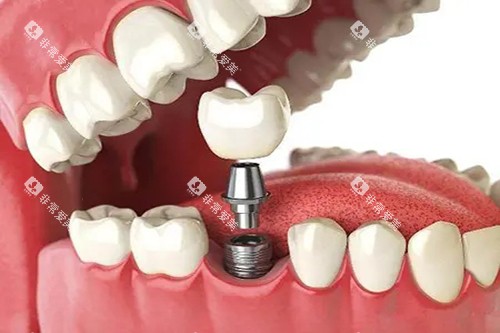

种植牙